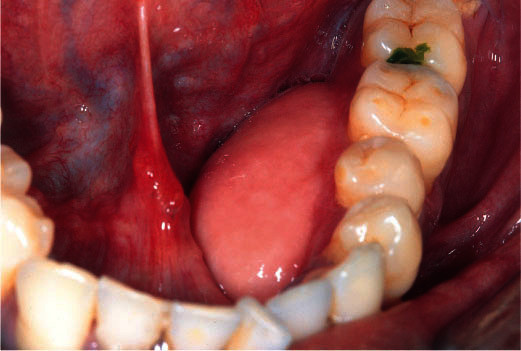

Lumps on the Jaw

Feel a lump on the roof of your mouth or gum, and not sure why it’s there? Lumps on the roof of your mouth or along your gumline may be the only jaw cancer symptoms you experience. While a lump could be an infection or benign growth, these lumps could also be a sign that cancer is developing on the jawbone beneath the mouth's soft tissues. If you notice a new lump inside your mouth and it doesn't resolve itself in two weeks, reach out to your dental professional.